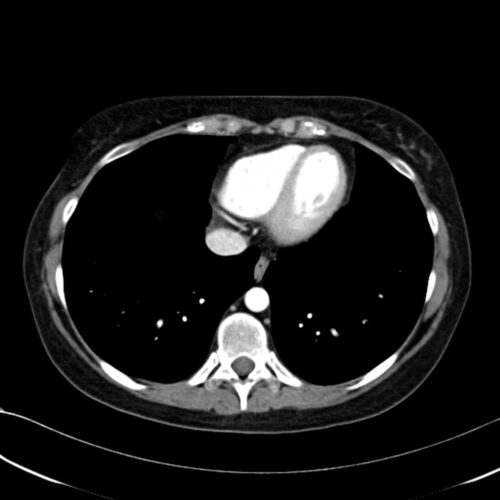

Zur Lokalisation eines Phäochromozytoms kann eine Computertomografie oder MRT des Adbomens eingesetzt werden. Eventuell kann eine selektive Blutentnahme helfen, eine fragliche Seitenlokalisation zu klären.

Neben dem Ausschluss einer Hormonaktitivät besteht die Diagnostik hautpsächlich in der Lokalisationsfindung, die mittels CT oder kontrastmittelverstärkter MRT erreicht werden kann. Die Indikation zu einer Operation ergibt sich primär aus der Größe eines Befundes. Bis zu 3cm große Inzidenatalome werden alle 6 Monate kontrolliert, ab 5 cm besteht der Verdacht auf ein Nebennierenkarzinom. Sollte sich bei der Operation der Verdacht auf ein Nebennierenkarzinom bestätigen, werden zusätzlich die paraaortalen und parakavalen Lymphknoten ausgeräumt und eine adjuvante Chemotherapie angeschlossen und das Tumorbett bestrahlt.